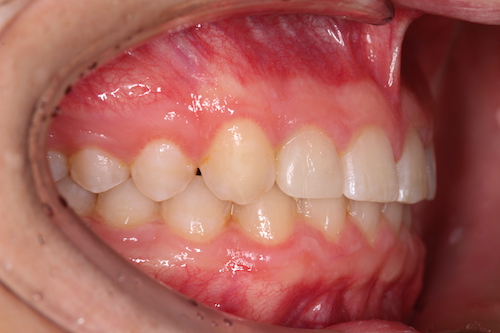

Частая ситуация, когда в общем все не плохо, но чего- то не хватает для идеала. Основной жалобой пациента было наличие выраженных промежутков на верхней челюсти, неровность положения зубов, глубокое перекрытие передних нижних резцов. Причина наличия промежутков заключалась в недостаточном размере по ширине боковых резцов верхней челюсти. именно поэтому после подъема высоты прикуса, нормализации наклонов зубов в переднем отделе, коррекции высоты перекрытия резцов, и доведение идеальных контактов в боковых отделах мы увеличили размер боковых резцов за счет композитного материала. Срок лечения 1 год.

До

После